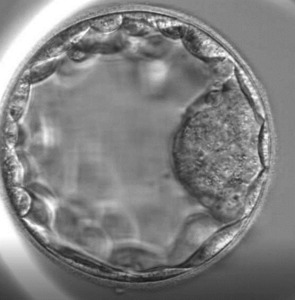

• If you are wondering what is a blastocyst, it is an embryo that has reached the stage of the blastocyst — an empty structure with an inner cell mass and outer layer of cells. At Day 5 of development in the incubator, the blastocyst embryo is larger and contains more cells than a Day 3 embryo. Understanding blastocyst vs embryo helps couples see why this stage can increase implantation opportunities during blastocyst IVF.

In conventional IVF, embryos are transferred on Day 3, whereas blastocyst IVF transfers occur on Day 5 at the blastocyst stage. Longer culture allows embryologists to select embryos with the best implantation potential, increasing pregnancy rates and reducing multiple pregnancies.

Blastocysts are evaluated based on size, cell number, and inner cell mass quality to select the best embryos for transfer or freezing.